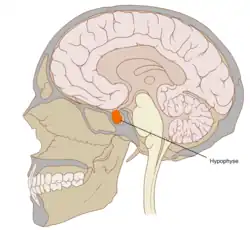

L'hypophyse se trouve dans une cavité osseuse, la fosse hypophysaire qui se situe dans l'os sphénoïde. Elle est protégée par la selle turcique. Elle est reliée à une autre partie du cerveau appelée l'hypothalamus par une tige hypophysaire (également appelée tige pituitaire). Elle produit des hormones qui gèrent une large gamme de fonctions corporelles, dont les hormones trophiques qui stimulent les autres glandes endocrines. Cette fonction lui a valu de se faire appeler par les scientifiques « glande maîtresse » du corps, mais aujourd'hui on sait que l'hypophyse est régulée par les hormones (neuro-hormones) émises par l'hypothalamus.

Chez l'être humain l'hypophyse mesure environ 10 millimètres de diamètre et pèse environ 0,5 gramme[3].

Anatomie

L'hypophyse est divisée en deux lobes : l'antéhypophyse (adénohypophyse) en avant, et la posthypophyse (neurohypophyse) en arrière. L'adénohypophyse dérive du plafond de la cavité buccale primitive (stomodeum), tandis que la neurohypophyse est une extension de l'hypothalamus, relié à celui-ci par la tige pituitaire, et contient les axones de neurones dont les corps cellulaires se trouvent dans l'hypothalamus. On peut également trouver entre l'antéhypophyse et la posthypophyse, une troisième structure, l'hypophyse intermédiaire, bien développée chez certaines espèces animales[Lesquelles ?] : chez l'humain, l'hypophyse intermédiaire (pars intermedia) est seulement visible en période fœtale et jusqu'à l'âge de dix ou vingt ans ; chez l'adulte, il subsiste quelques structures kystiques (follicules, restes de la poche de Rathke), ainsi qu'un infiltrat chromatophile basophile.